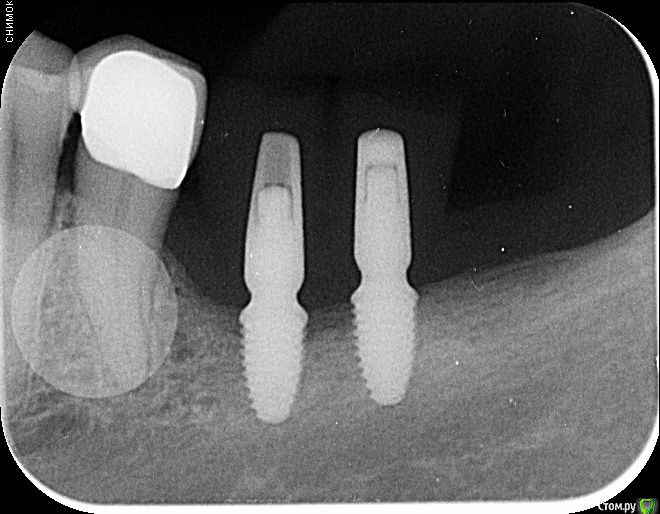

Fin Опубликовано 29 июля, 2020 Поделиться Опубликовано 29 июля, 2020 Здравствуйте коллеги. У пациента отсутствуют зуб 3.5 и 3.6. и высоко расположенный канал тройничного нерва. Что бы вы сделали в данном случае? Наращивать ширину? Ставить ССТ? Ссылка на комментарий

annda Опубликовано 3 августа, 2020 Поделиться Опубликовано 3 августа, 2020 (изменено) Стоял до этих имплантатов суперлайн коротыш 7мм,одиночка.Заколебались с раскруткой винта,ходила каждый месяц.Плюнула,решили выкрутить,переставить на эти.КТ после удаления. Изменено 3 августа, 2020 пользователем annda 1 Ссылка на комментарий

annda Опубликовано 4 августа, 2020 Поделиться Опубликовано 4 августа, 2020 Что-то с загрузкой пошло не так,извините.Контроль после постановки и контроль с абатментами(через 3 месяца) Ссылка на комментарий